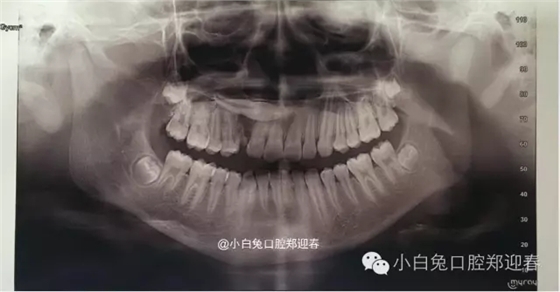

術(shù)前全景片

全景片顯示:53滯留,13橫位阻生,但是全景片反映不出真實的阻生尖牙的解剖位置,因此要借助CT進(jìn)行定位。